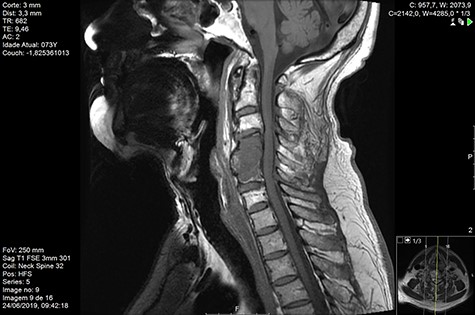

Computed tomography (CT) (Figs 1–3) and magnetic resonance imaging (MRI) (Figs 4–6) of the cervical spine were performed and revealed a lytic lesion involving most of C4, C5 and C6 vertebral bodies with bilateral extension to the posterior spinal elements of C4 and C5 and complete disruption of C4-C5 and C5-C6 intervertebral discs.

The Spinal Instability Neoplastic Score (SINS) [4, 6, 7] for assessing spinal instability from metastatic disease was used and the lesion was deemed unstable (SINS 13), with impending risk of increased neurological damage.

Findings from laboratory tests (serum protein electrophoresis) led to the diagnosis of MM. The patient was placed on a Philadelphia c-spine collar and underwent local 3D external-beam radiotherapy (20Gy in five fractions).